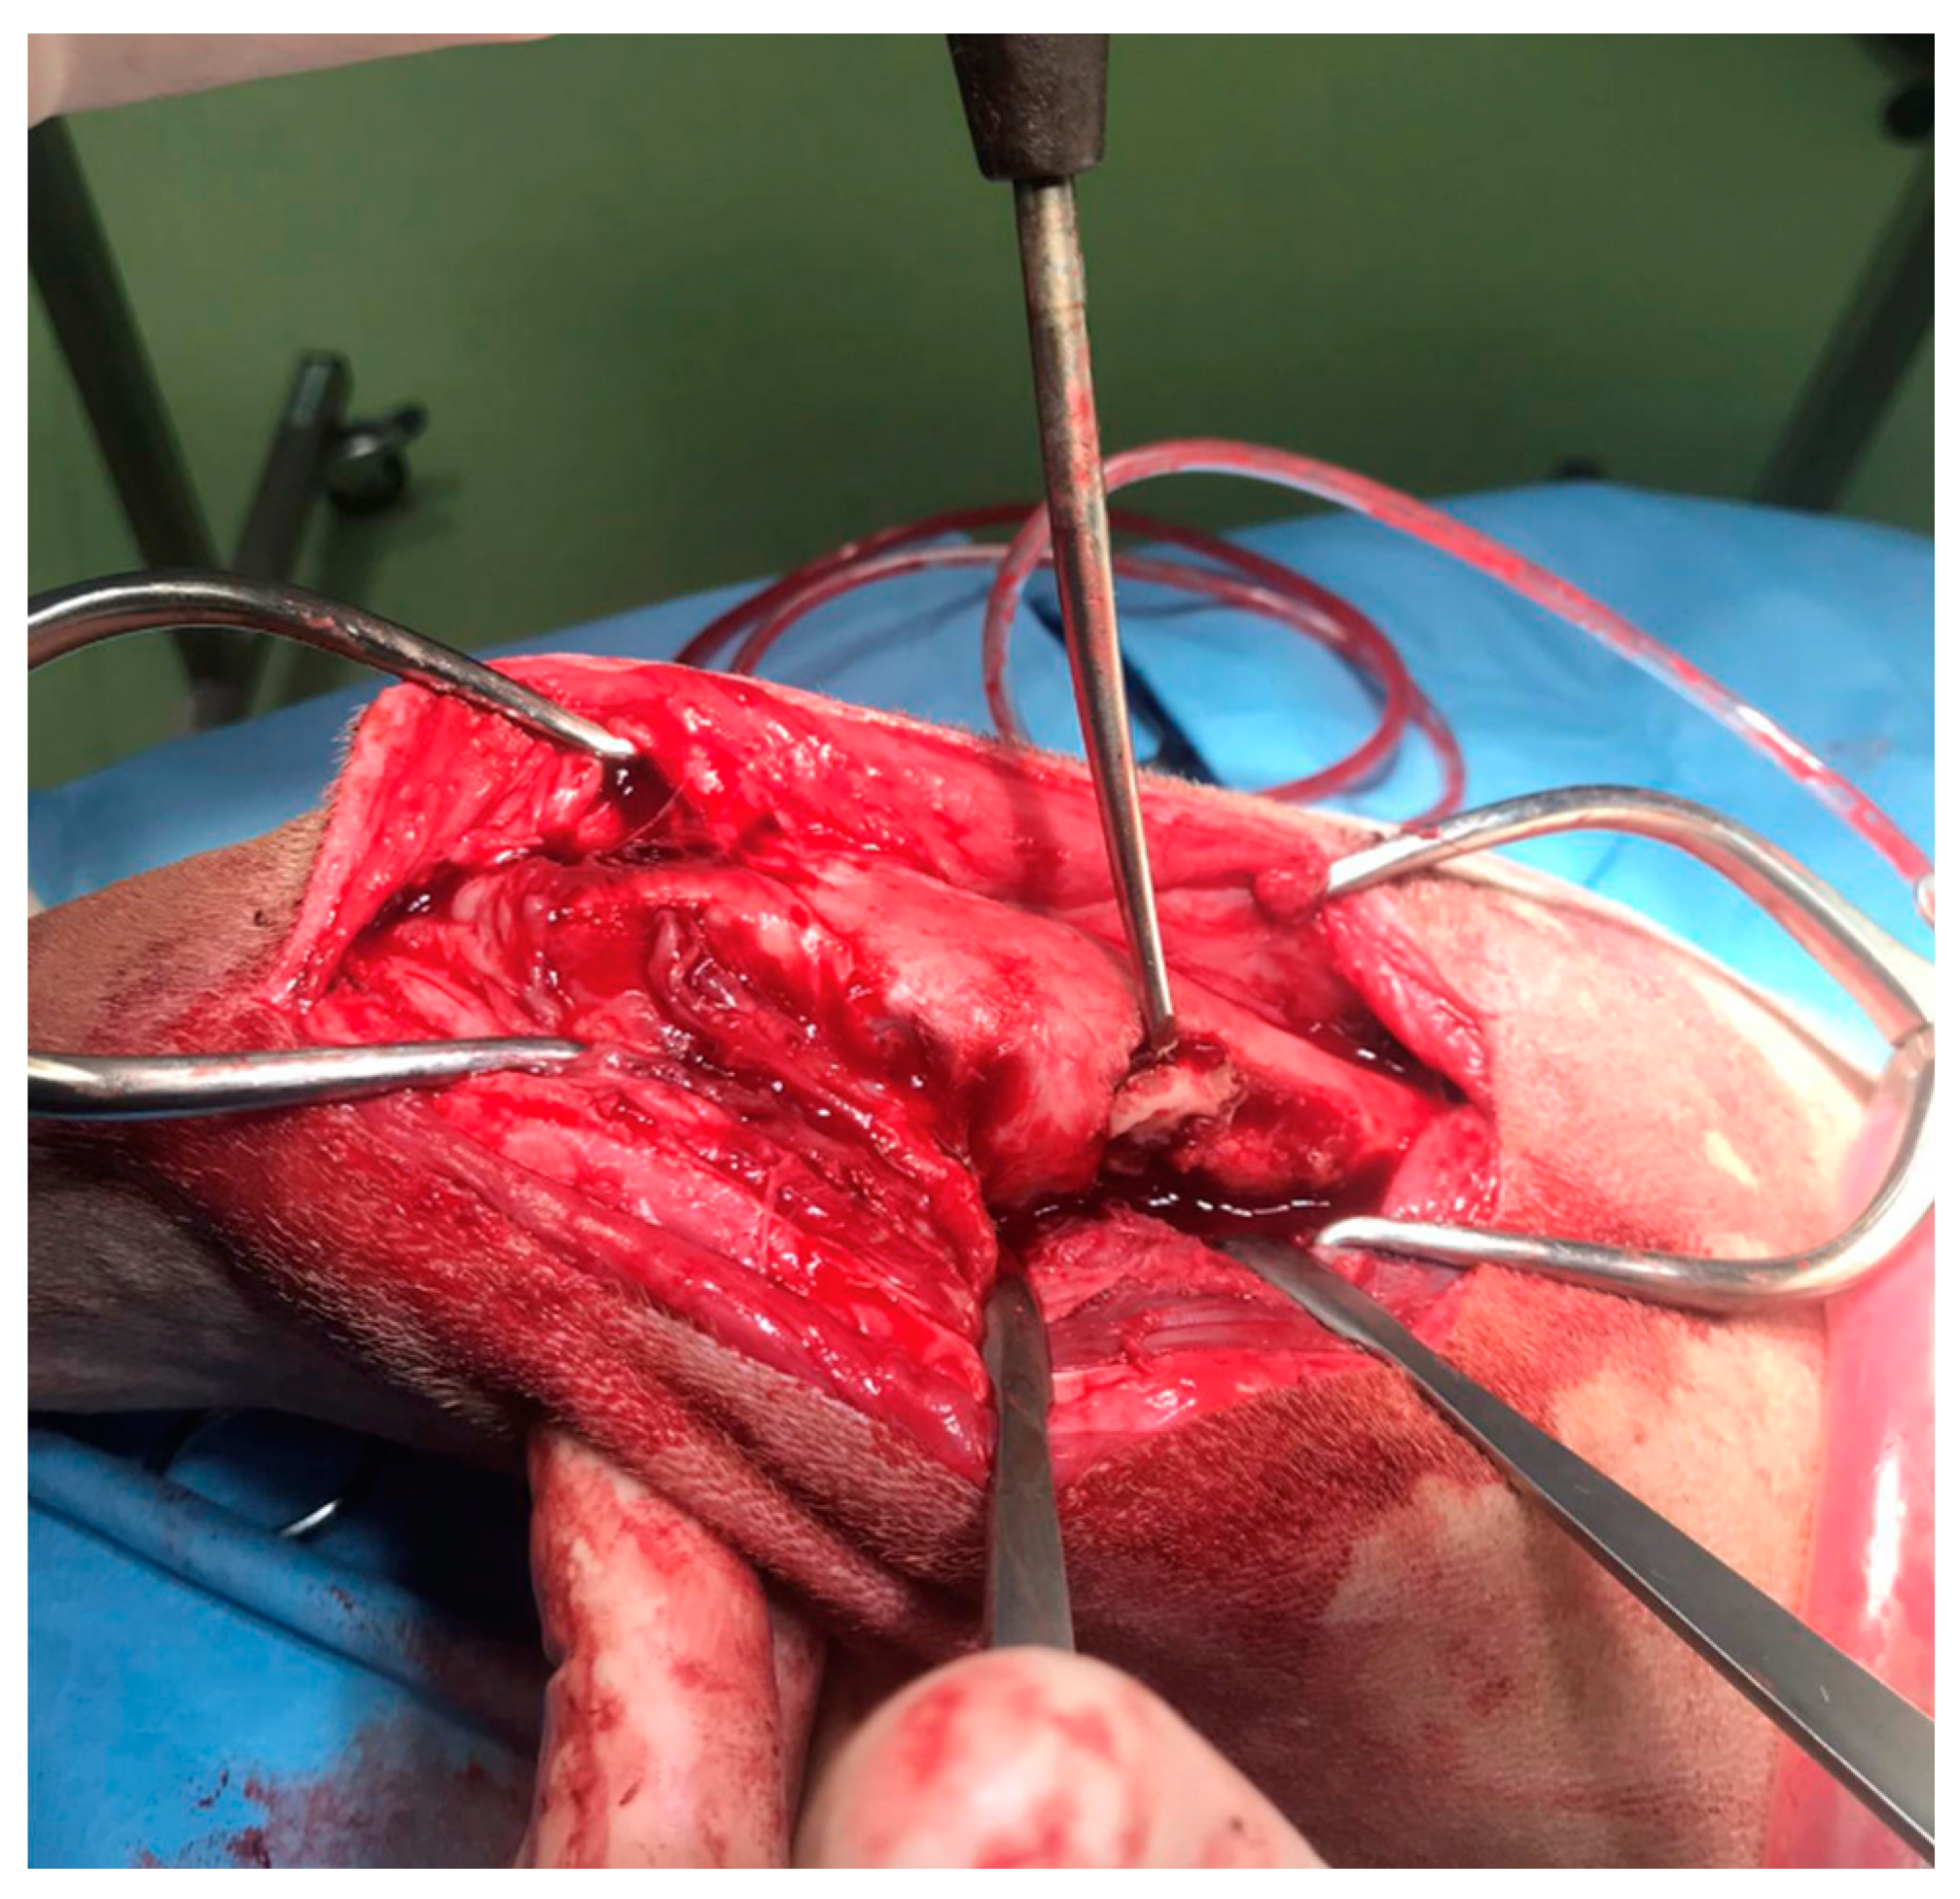

In agreement with the owner, a surgical procedure was performed in order to remove the bone sequestrum, debride necrotic tissues and perform a copious lavage of the affected region (Figure 4). A modified Robert Jones splint was applied for 48 hours after the surgery. The patient was hospitalized for 48 hours and then discharged with a specific antibiotic therapy (nitrofurantoin 4 mg/kg PO twice daily) and anti-inflammatory therapy (meloxicam 0.1 mg/kg PO once daily). The antibiotic and anti-inflammatory therapy was prescribed and administered to the patient for 30 days once the patient was discharged.

Figure 4. The intraoperative image of the bone sequestrum and of surgical debridement of the necrotic tissue.